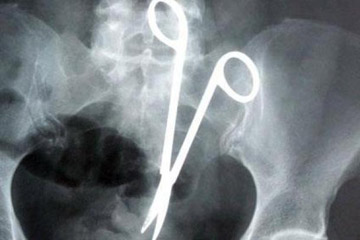

أطباء ينسوا مقص في بطن مريض منذ عام 1998!

ظل مقص جراحي في بطن فيتنامي طيلة 18 عاما دون أن يدري إلى أن استخرجه الأطباء أخيرا.

ونقل التلفزيون الرسمي عن ما فان نهات (54 عاما) قوله إن الأطباء نسوا المقص على الأرجح في بطنه عام 1998 بعدما خضع لجراحة عاجلة بعد حادث مروري.

وقال نهات إنه كان يشعر بألم على فترات وإن الأطباء وصفوا له دواء لقرحة المعدة إلا أن أشعة سينية أجريت له بنهاية العام الماضي أظهرت السبب: مقص جراحي.